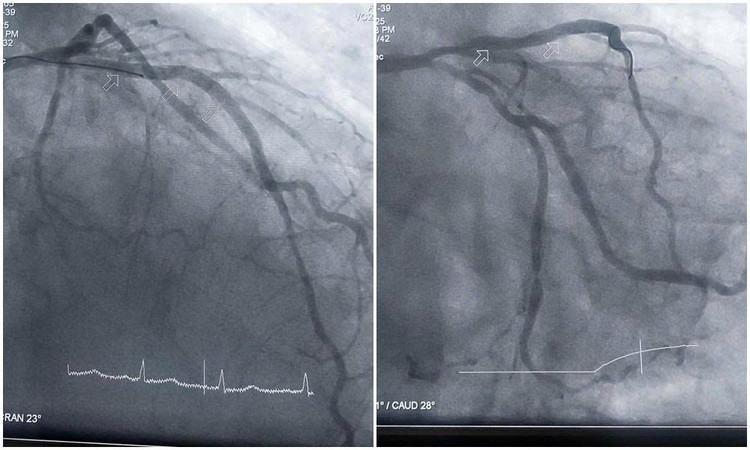

Đoạn mạch hẹp tắc tái thông sau can thiệp nong bóng và đặt stent - Ảnh BVCC

Kíp can thiệp tập trung xử trí tổn thương nặng, luồn dây dẫn qua đoạn mạch bị vôi hóa, sử dụng dụng cụ chuyên dụng để nong bóng, từng bước mở lại lòng mạch bị hẹp nặng.

Việc vượt qua các đoạn mạch vôi hóa cứng là thách thức lớn, song bằng kinh nghiệm và sự kiên trì, các bác sĩ đã đặt thành công stent vào đoạn động mạch liên thất trước bị nặng nề nhất, giúp tái thông dòng máu nuôi tim. Sau can thiệp, tình trạng huyết động của người bệnh dần cải thiện, nhịp tim ổn định, hết đau tức ngực.